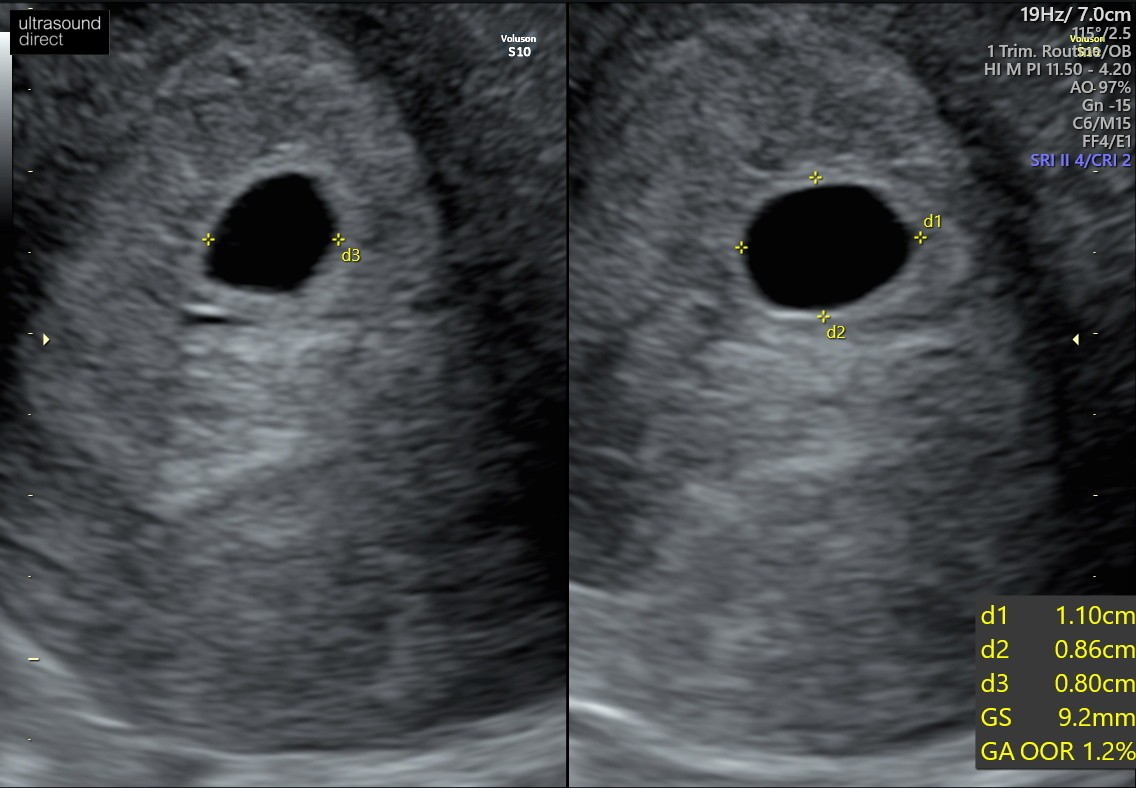

A to z mojego skanu (25/09)

Witam , jestem w Uk - stad moje mega obawy chyba. Ostatnia miese miałam 7/08. Test pozytywny 4/09 w dzień spodziewanej miesiączki. Według obliczeń poszliśmy na usg w 7+6 tyg (25.09). Babeczka robiąc usg wykryła puste jajo płodowe z nawiązką krwi obok jaja. Powiedziała ze może to być puste, małe jajo płodowe albo 5 tydz ciąży dopiero, z tym ze nie jest widoczne ciałko żółte. Dwa dni po badaniu plamienia różowe , potem brązowe, bol brzucha pojechaliśmy do szpitala - dalej pusto ale mówią , plamienia to normalka, bol brzucha to normalka No i czekać za dwa tyg scan. Według moich obliczeń mega niemożliwością jest żebyśmy byli w piątym tyg dopiero bo sex uprawialiśmy 19/08 (20/08 wypadała ovulacja) prosze bez ocianiania ale potem nie mieliśmy sexu do 3/9 dzień nastepny robiłam test który wyszedł pozytywnie. Ja rozumiem ze może się wszystko poprzesuwać ale cykle mam co 28 dni, regularne. No i te plamienia teraz z bolącymi plecami i podbrzuszem. Zamartwiam się totalnie. Mial ktoś taka sytuacje ? Kiedy wszystko wydaje się kalendarzykowo a jednak te 2 wielkie tyg wszystko się przesunęło ??